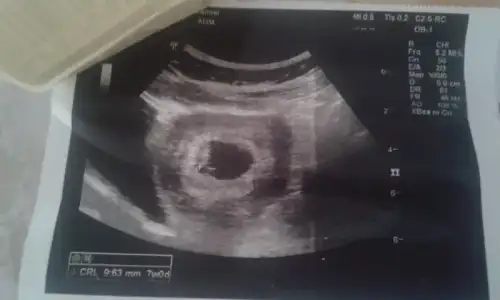

Bunlar da benim miniklerim. 6. haftada cekilmisti.:KK200:

Henüz kalp atışlarını görmedik salıya kismetse...